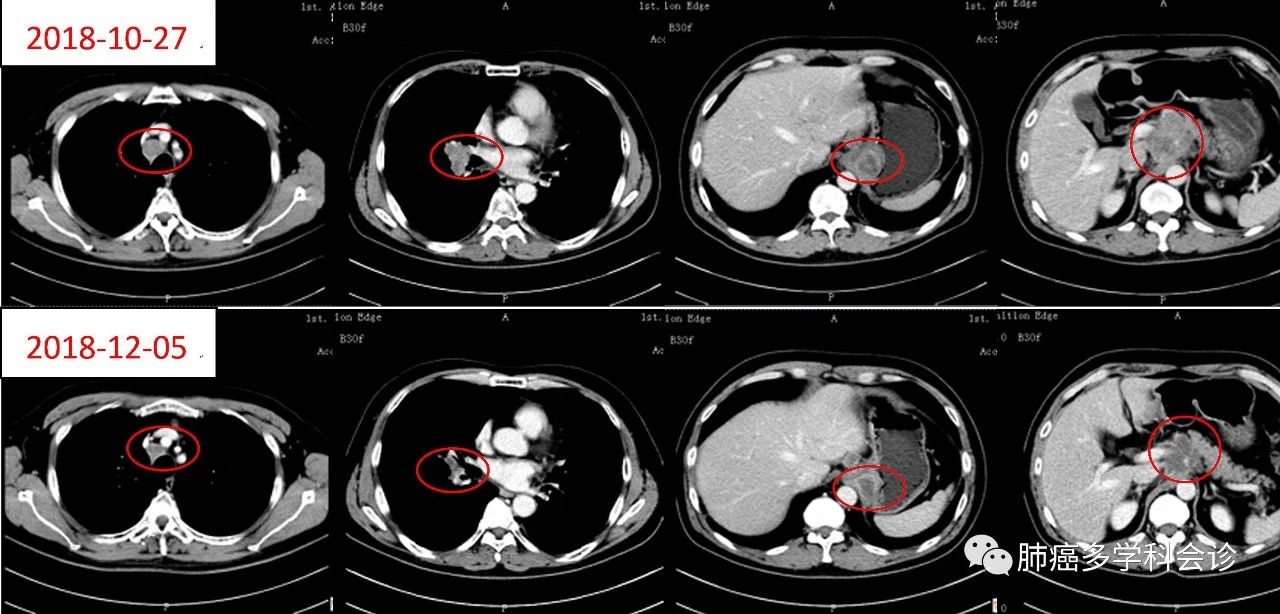

以下是患者口服西奥罗尼前后胸和腹部肿瘤病灶的变化:

1.jpg最近还有另外一例经反复治疗后疾病进展的广泛期小细胞肺癌患者,经西奥罗尼治疗后获得了部分缓解!